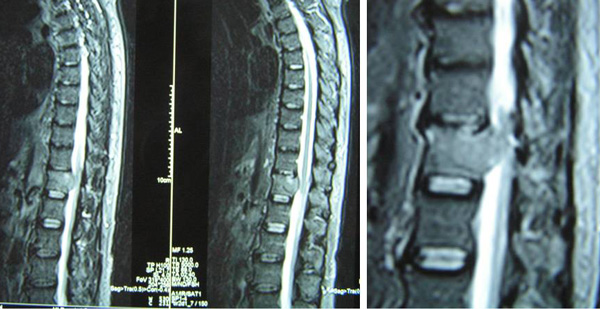

6. There is a lytic lesion in the vertebral body of T12. Fracture of the superior endplate of T12 is noted. This probably represents a bony metastasis.

On 13 August 2011, MRI of the thoracic spine was carried out. The result confirmed a lesion measuring 3.5 x2.4 x 2.2 cm in T12 vertebra. The mass extends into the spinal canal and displacing the nerve roots. Findings are in keeping with a metastatic lesion.

TS was referred to an oncologist who suggested that he undergo 10 times of radiation treatment to this back. This is to relieve the minor pains he complained about.